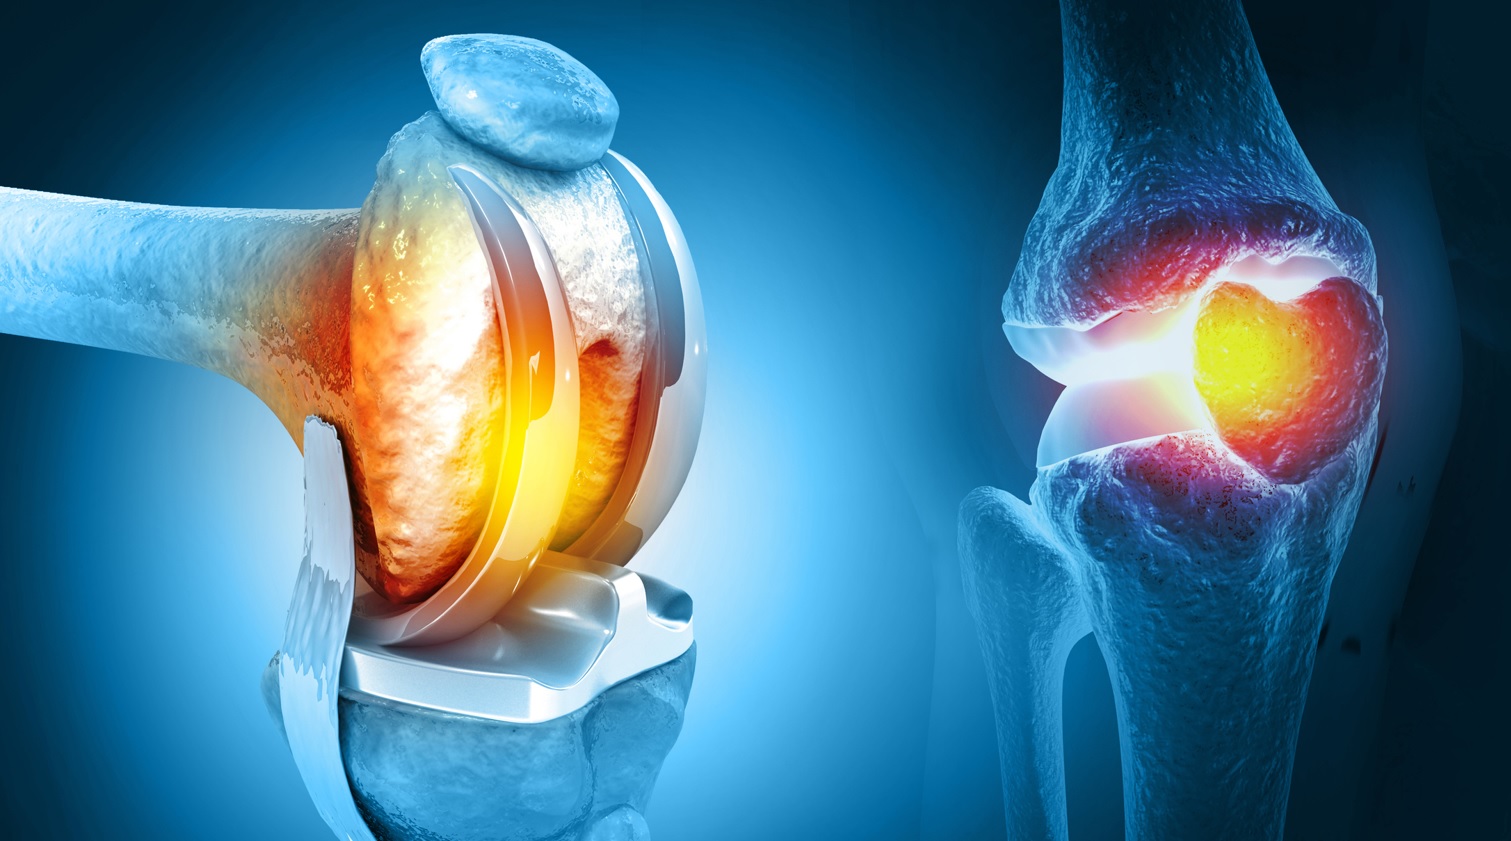

تعویض مفصل زانو یک جراحى بازسازى مفصل است که در آن سطوح فرسوده استخوان ران، درشتنى و کشکک برداشته مىشود و با قطعات مصنوعى از جنس فلز و پلیاتیلن جایگزین مىگردد. هدف اصلى این روش کاهش درد مزمن، اصلاح تغییر شکل زانو و بازگرداندن دامنه حرکتى کاربردى براى راه رفتن، نشستن و برخاستن است. برخلاف تصور عموم، این جراحى فقط زمانى انجام مىشود که درمانهاى غیرجراحى مانند دارودرمانى، تزریقات، اصلاح سبک زندگى و فیزیوتراپى دیگر پاسخگو نباشند.

موفقیت تعویض مفصل زانو به چند عامل وابسته است شامل مهارت جراح، کیفیت پروتز، وضعیت سلامت عمومى بیمار و مهمتر از همه برنامه توانبخشى دقیق بعد از عمل. پروتزهاى مدرن به گونهاى طراحى شدهاند که سالها دوام داشته باشند و امکان حرکت طبیعى را فراهم کنند. با این حال، مراقبت صحیح از مفصل مصنوعى و انجام منظم فیزیوتراپى زانو نقش تعیینکنندهاى در طول عمر آن دارد.

انواع پروتز زانو

پروتزها به طور کلى به دو نوع نیمه و کامل تقسیم مىشوند. در تعویض نیمه مفصل زانو فقط یک بخش آسیبدیده تعویض مىشود که براى بیماران با آرتروز محدود مناسب است. در تعویض کامل مفصل زانو هر سه بخش مفصل شامل بخش داخلى، خارجى و کشکک بازسازى مىشود و بیشتر براى آرتروز پیشرفته کاربرد دارد.

انتخاب نوع پروتز بر اساس سن بیمار، سطح فعالیت، میزان تخریب مفصل و نظر تیم جراحى انجام مىشود. برخى پروتزها با تکنولوژى حرکت تطبیقى ساخته شدهاند که فشار را بهتر توزیع مىکنند و برخى دیگر براى بیماران فعالتر طراحى شدهاند. در هر حالت، کیفیت توانبخشى بعد از عمل تاثیر مستقیم بر عملکرد نهایى پروتز دارد.